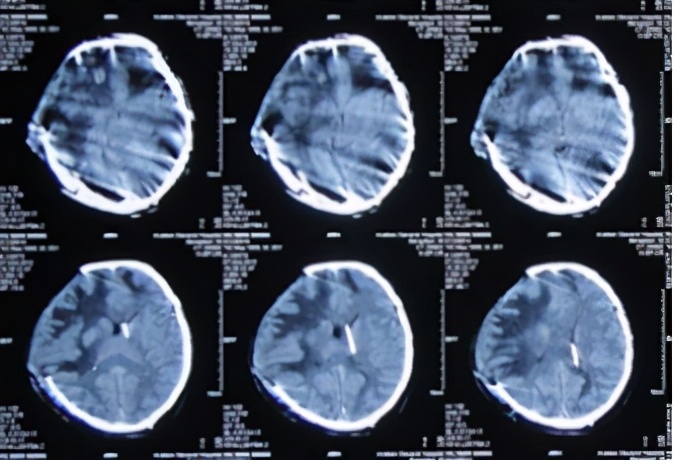

一、在李小勇脑脊液中心入院前病史

图-1:2013年9月17日术前头CT

图-2:2013年9月17日术后头CT